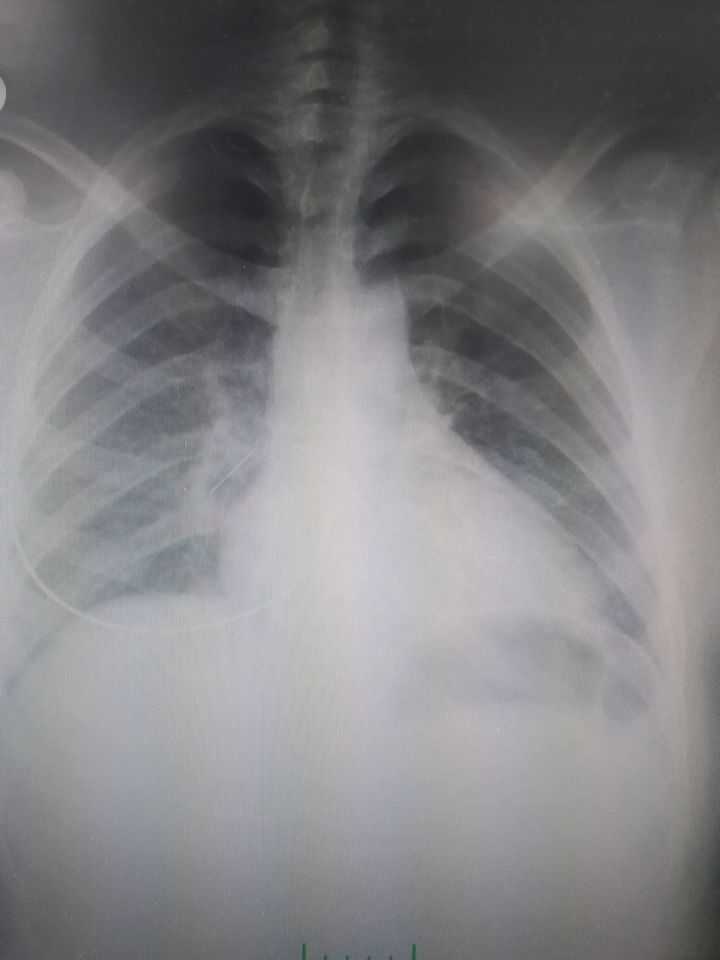

She swallowed a needle.

Right bronchial